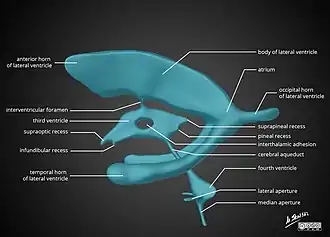

Cerebral aqueduct

The cerebral aqueduct is the part of the ventricular system which links the third ventricle (rostrally) with the fourth ventricle (caudally); as such it is responsible for continuing the circulation of cerebrospinal fluid. The cerebral aqueduct is a narrow channel located between the tectum and the tegmentum, and is surrounded by the periaqueductal grey,[9] which has a role in analgesia, quiescence, and bonding. The dorsal raphe nucleus (which releases serotonin in response to certain neural activity) is located at the ventral side of the periaqueductal grey, at the level of the inferior colliculus.

The nuclei of two pairs of cranial nerves are similarly located at the ventral side of the periaqueductal grey – the pair of oculomotor nuclei (which control the eyelid, and most eye movements) is located at the level of the superior colliculus,[10] while the pair of trochlear nuclei (which helps focus vision on more proximal objects) is located caudally to that, at the level of the inferior colliculus, immediately lateral to the dorsal raphe nucleus.[9] The oculomotor nerve emerges from the nucleus by traversing the ventral width of the tegmentum, while the trochlear nerve emerges via the tectum, just below the inferior colliculus itself; the trochlear is the only cranial nerve to exit the brainstem dorsally. The Edinger-Westphal nucleus (which controls the shape of the lens and size of the pupil) is located between the oculomotor nucleus and the cerebral aqueduct.[9]